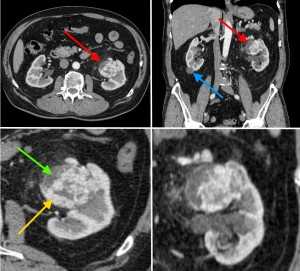

КТ-признаки рака (гипернефромы) почки в артериально-паренхиматозную фазу контрастирования. На изображениях в верхнем ряду стрелкой красного цвета отмечено новообразование в виде узла с неоднородной структурой, синей стрелкой - простая киста в области нижнего полюса справа. В нижнем ряду желтой стрелкой выделен мягкотканный компонент, накапливающий контраст и интенсивно усиливающийся. Зеленой стрелкой - кистозный компонент.